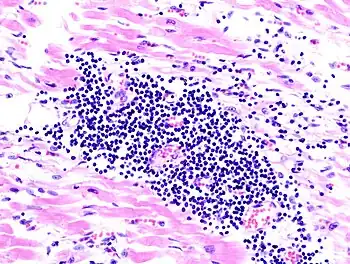

| A microscope image of myocarditis at autopsy in a person with acute onset of heart failure | |

The gold standard is the biopsy of the myocardium, in general done in the setting of angiography. A small tissue sample of the endocardium and myocardium is taken and investigated. The cause of the myocarditis can be only identified by a biopsy. Endomyocardial biopsy samples are assessed for histopathology (how the tissue looks like under the microscope): myocardial interstitium may show abundant edema and inflammatory infiltrate, rich in lymphocytes and macrophages. Focal destruction of myocytes explains the myocardial pump failure.[10] In addition samples may be assessed with immunohistochemistry to determine which types of immune cells are involved in the reaction and how they are distributed. Furthermore, PCR and/or RT-PCR may be performed to identify particular viruses. Finally, further diagnostic methods like microRNA assays and gene-expression profile may be performed.